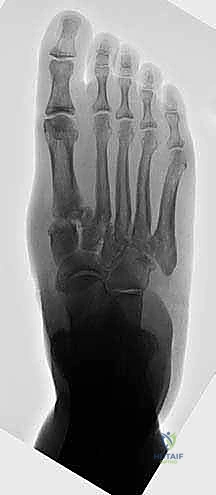

- الأشعة السينية أثناء الوقوف (Weight-bearing X-rays): وهي أهم أداة تشخيصية. الأشعة العادية والسرير فارغ لا تظهر المشكلة الحقيقية؛ يجب التقاط الأشعة والمريض يقف ليتحمل وزن الجسم، مما يظهر الانهيار الفعلي للمفاصل وتضيق المسافات بين العظام.

- الأشعة المقطعية (CT Scan): توفر صوراً ثلاثية الأبعاد للعظام، وهي ضرورية جداً للتخطيط الجراحي الدقيق وتحديد مدى التلف العظمي والزوايا المطلوبة للتثبيت.